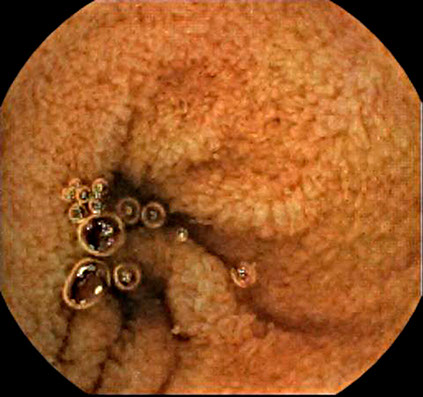

Case Gallery